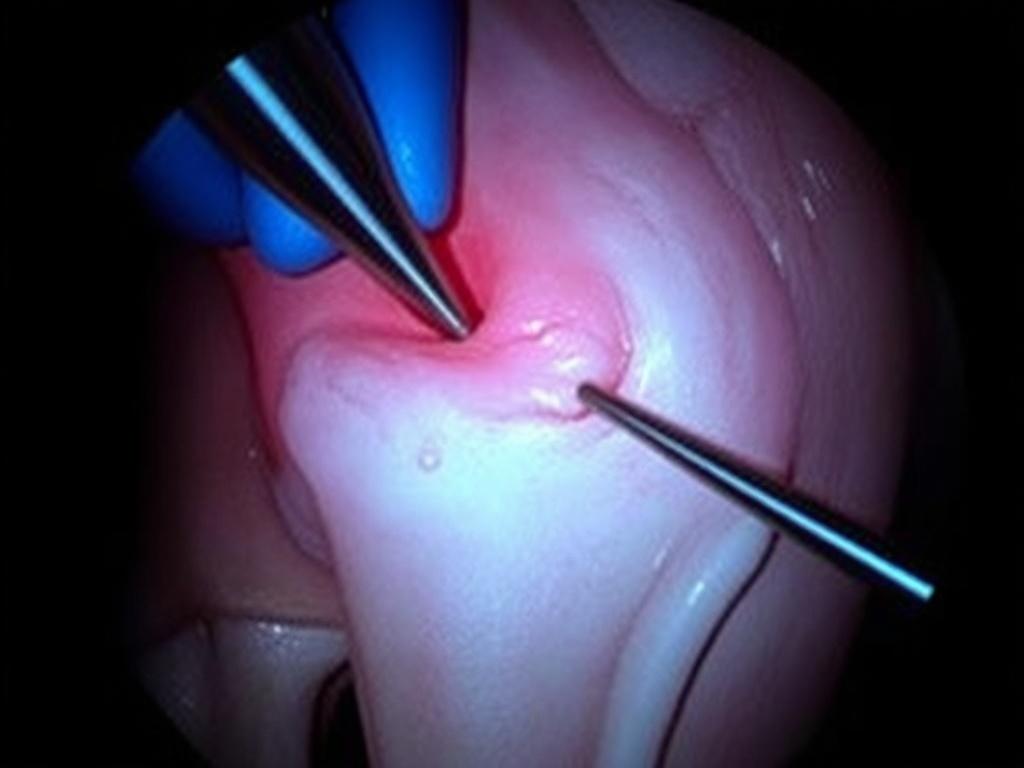

Пациент получает спинальную или проводниковую анестезию. Хирург делает 2–3 прокола по 5–7 мм. Артроскоп показывает картинку на экране. Хирург оценивает разрыв и принимает тактическое решение. Края разрыва освежают, чтобы включить заживление, потом ставят фиксаторы. Это могут быть «якоря», мини-«стрелы» или нити, проведенные специальными иглами. Узлы прячут вне зоны трения. Сустав промывают, проколы закрывают полосками и маленькими швами. Вся операция обычно занимает 30–60 минут.